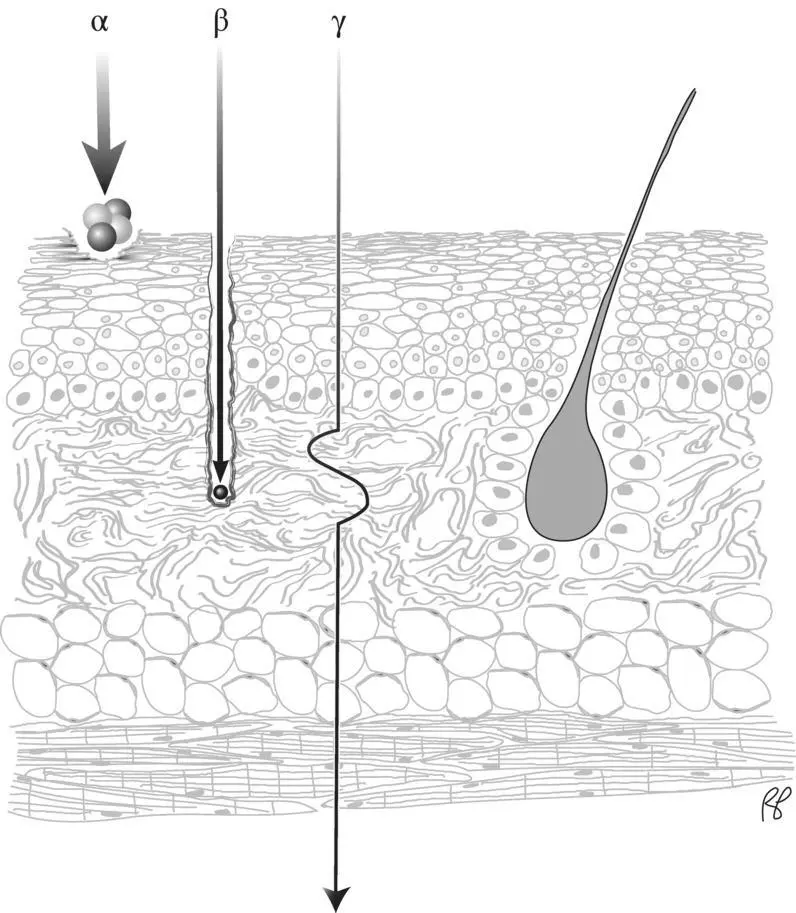

Figure 2.7 Penetrating radiation and nonpenetrating radiation.

The term penetrating radiationmay be used to describe X‐ray and gamma radiation, as they have the potential to penetrate considerable thickness of a material. Although we have just described some of the many ways photons interact with matter, the likelihood of any of these interactions occurring over a short distance is small. An individual photon may travel several centimeters or farther into tissue before it interacts. In contrast, charged particles (alpha, beta) undergo many closely spaced interactions. This sharply limits their penetration ( Figure 2.7).

Interaction of charged particles with matter

Because of the strong electrical force between a charged particle and the atoms of an absorber, charged particles can be stopped by matter with relative ease. Compared to photons, they transfer a greater amount of energy in a shorter distance and come to rest more rapidly. For this reason, they are referred to as nonpenetrating radiation(see depiction of alpha and beta particles in Figure 2.7). In contrast to a photon of 100 keV which has a HVL of 4 cm in soft tissue, an electron of this energy would penetrate less than 0.00014 cm in soft tissue [1].